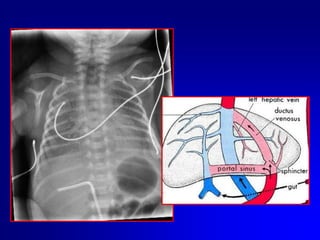

Eseguire sempre controllo radiografico o ecografico della posizione del catetere..

Se non è possibile passare il dotto venoso lasciare il catetere circa 2 cm dentro il piano cutaneo e valutare il ritorno ematico.

Il CVO può essere mantenuto per un tempo massimo di 14 giorni. Nei VLBW sarebbe preferibile rimuoverlo entro 7-8 giorniApplicare suzione lieve alla siringa.Se non vi è ritorno ematico vi può essere un coagulo sulla punta, quindi sfilare il catetere in aspirazione, rimuovere il cagulo e reinserire. Se vi è ritorno ematico, continuare ad inserire il catetere fino alla distanza stimata. Se il catetere incontra qualche ostruzione prima della distanza desiderata:Cause più comuniEntrato nel sistema portaleIncuneato in una branca intraepatica della vena ombelicaleRetrarre il catetere di 2-3 cm ruotarlo delicatamente e reinserirlo Se il catetere è nel circolo portale lasciare li il catetere; reinserire un altro 5–Fr nello stesso vaso. Una volta che il catetere è nella posizione giusta  si sfila quello in porta. Questa procedura ha successo nel 50% dei casi.

Eseguire semprecontrollo radiografico o ecografico della posizione del catetere..

Se nonè possibile passare il dotto venoso lasciare il catetere circa 2 cm dentro il piano cutaneo e valutare il ritorno ematico.

Il CVO puòessere mantenuto per un tempo massimo di 14 giorni. Nei VLBW sarebbe preferibile rimuoverlo entro 7-8 giorniApplicare suzione lieve alla siringa.Se non vi è ritorno ematico vi può essere un coagulo sulla punta, quindi sfilare il catetere in aspirazione, rimuovere il cagulo e reinserire. Se vi è ritorno ematico, continuare ad inserire il catetere fino alla distanza stimata. Se il catetere incontra qualche ostruzione prima della distanza desiderata:Cause più comuniEntrato nel sistema portaleIncuneato in una branca intraepatica della vena ombelicaleRetrarre il catetere di 2-3 cm ruotarlo delicatamente e reinserirlo Se il catetere è nel circolo portale lasciare li il catetere; reinserire un altro 5–Fr nello stesso vaso. Una volta che il catetere è nella posizione giusta si sfila quello in porta. Questa procedura ha successo nel 50% dei casi.